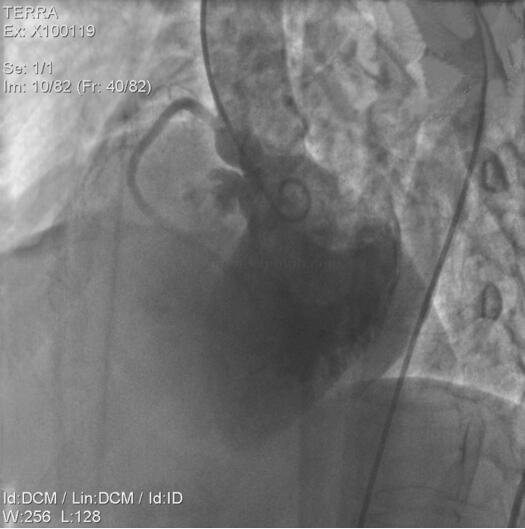

术中压力曲线见图2-9。

图2-9 心导管术术中压力曲线

(1)左心室造影

显示室间隔膜部瘤,室间隔缺损,破口直径约4mm,见左向右分流。冠状动脉造影显示正常冠状动脉(图2-11)。

封堵术前

图2-11 冠状动脉造影示正常冠状动脉

封堵术后